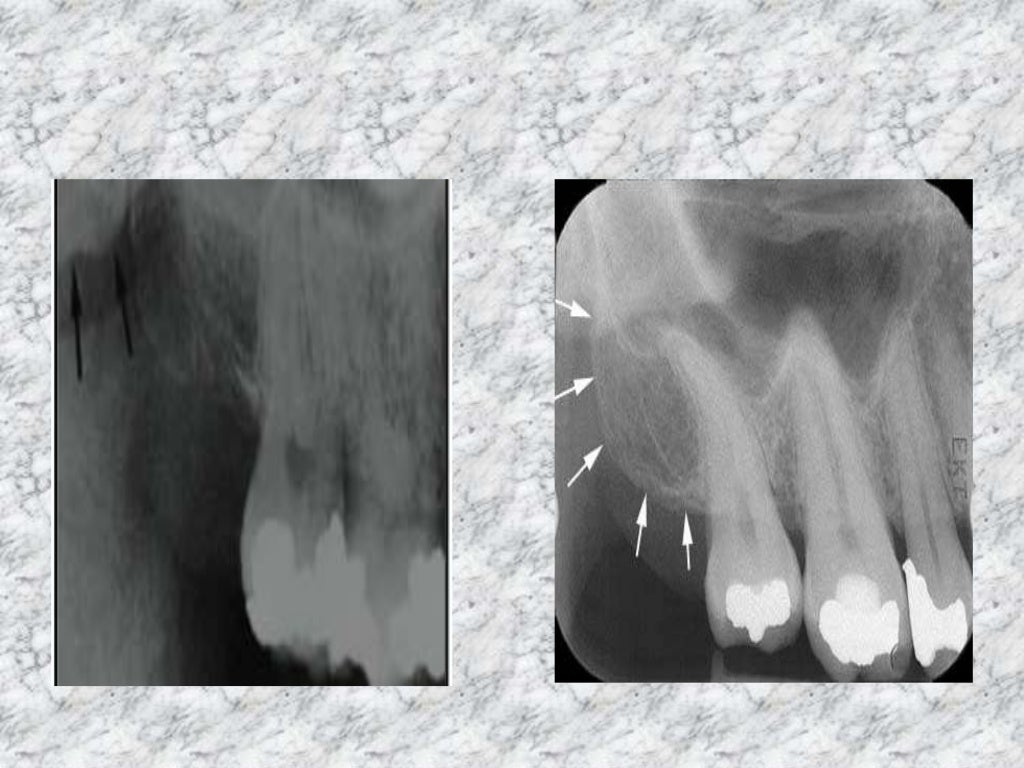

Radiopaque Landmarks on Mandibular Radiographs Dental Radiography Most Radiopaque The radiopacity values of gradia direct loflo, dentin and estelite flow q were close to that of 1 mm al. for most of the dental restorative materials, moderate radiopacity within the range of the replaced dental. What is the most radiopaque. periapical radiolucencies are most commonly odontogenic. What is the most radiolucent material? your patient points to. Most Radiopaque.